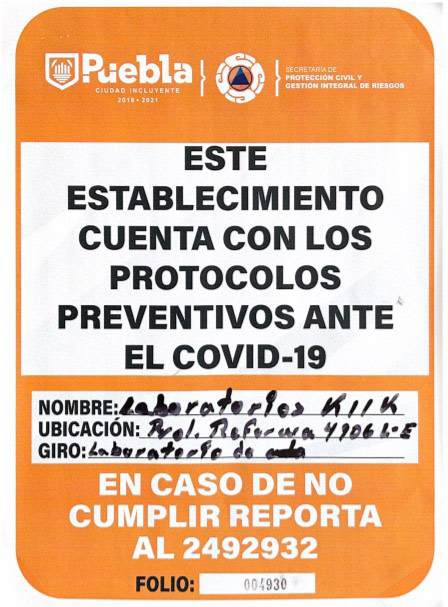

- Prolongación Reforma No. 4906 Local E. Col. La Libertad. Puebla, Pue.